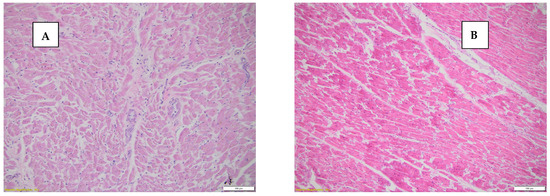

Although in the case of deaths by SCD, fiber fragmentation presents a characteristic histopathological change produced by acute myocardial ischemia, it was present in 57.5% (23 cases), but in the case of violent deaths, 5% (2 cases) presented myocardial fiber fragmentation (Figure 3).

Figure 3.

(A) Myocardial tissue with fragmented cardiac fibers, HE stain, 20×. (B) Myocardial tissue with intact, unfragmented fibers, HE stain, 20×.